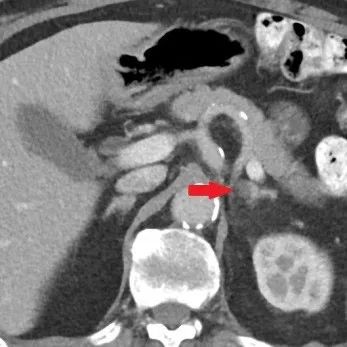

肾上腺腺瘤微波消融术中

图4. 微波针穿刺到位。